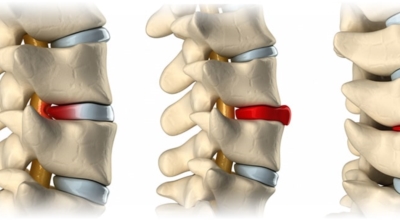

여러 개의 작은 척추뼈가 모여서 척추라는 인체의 기둥을 이루게 되어요. 척추뼈 사이에는 척추뼈끼리 부딪치는 것을 방지하는 쿠션 같은 역할을 하는 '디스크(disc)'라는 말랑말랑한 젤리 같은 구조물이 있는데 우리말로는 '추간판'이라고 하네요.

디스크(추간판)의 한가운데에는 젤리같이 찐득찐득한 '수핵'이라고 하는 성분이 들어 있어요. 그 주변에 수핵을 둘러싸는 '섬유륜'이라 하는 두꺼운 막이 있는데 디스크는 전체적으로 자동차의 타이어와 같은 형태라고 해요. 디스크는 일어선 상태에서는 중력을 받아 납작해져서 바깥쪽으로 약간 볼록한 형태가 된다고 해요.

디스크는 그 특수한 구조 때문에 웬만한 힘이 가해져도 효율적으로 쿠션 역할을 할 수 있겠습니다. 그러나 갑작스럽게 무거운 물건을 들어 올리거나, 부자연스러운 자세를 장시간 취하면 디스크에 무리한 힘이 가해지면서 디스크가 밖으로 돌출이 되게 돼요. 심한 경우 디스크를 감싼 막이 터지면서 그 안에 있는 수핵이 튀어나오게 돼요. 디스크는 대부분이 후방이나 후외방으로 돌출되는데 이 경우에 바로 곁에 있는 신경을 누르게 된다고 해요.

돌출된 디스크는 척추의 어느 부위에나 발생할 수 있답니다. 목에 생기면 '목 디스크', 등에 생기면 '등 디스크', 허리에 생기면 '허리 디스크'라고 부른다고 해요. 이와 같이 디스크가 돌출되어 신경을 눌러 요통 및 다리가 아프고 저린 증상을 일으키는 병을 '추간판 탈출증' 또는 '디스크 탈출증'이라고도 불리워요. 발생 빈도별로 보면 허리 디스크가 가장 흔해요. 그다음이 목 디스크입니다. 등 디스크는 드문 병이라고 하네요.